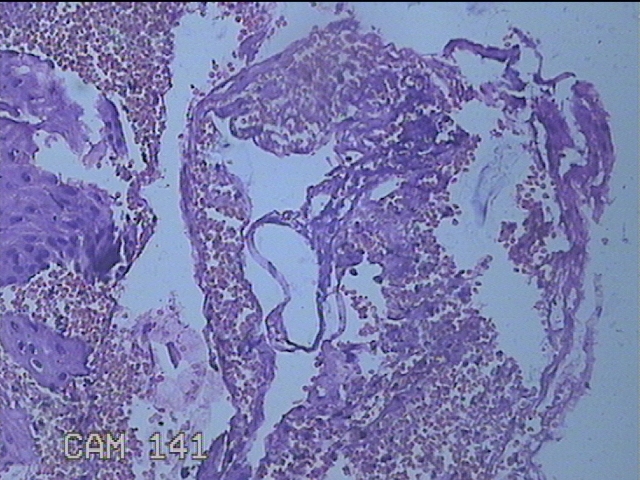

宫颈6点组织

性别

女

年龄

48岁

临床诊断

人乳头瘤病毒感染;慢性子宫颈炎

一般病史

发现高危HPV58及68阳性。

标本名称

大体所见

灰白粉红色红色组织1.3x0.3x0.2cm一块。

鳞状上皮低度病变。